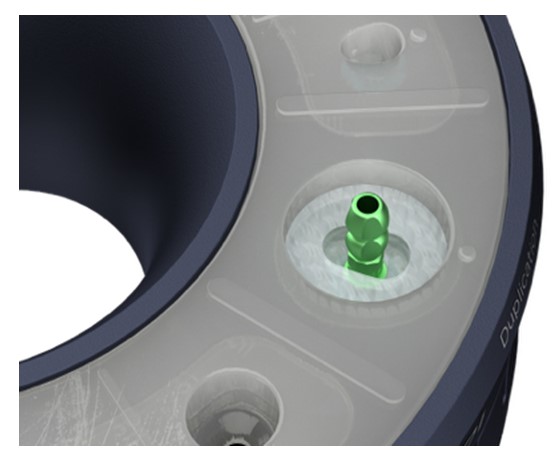

Asistentul instalează un bont temporar în puțul matriței cu codul corespunzător (E.g pS) la cel din fila de formă anatomică a ghidului (E.g pS).

El / Ea introduce apoi materialul compozit adecvat în spațiul deschis și vindecă ușor cu unul sau mai multe trepte.

Asistentul instalează un stâlp de imprimare a stocului în același puț al matriței care a fost folosit pentru fabricarea bontului personalizat de vindecare (de exemplu, pS).

El / Ea introduce apoi materialul compozit adecvat în spațiul deschis și vindecă ușor cu unul sau mai multe trepte.

Instalează în puțul de dublare un post de imprimare adecvat.